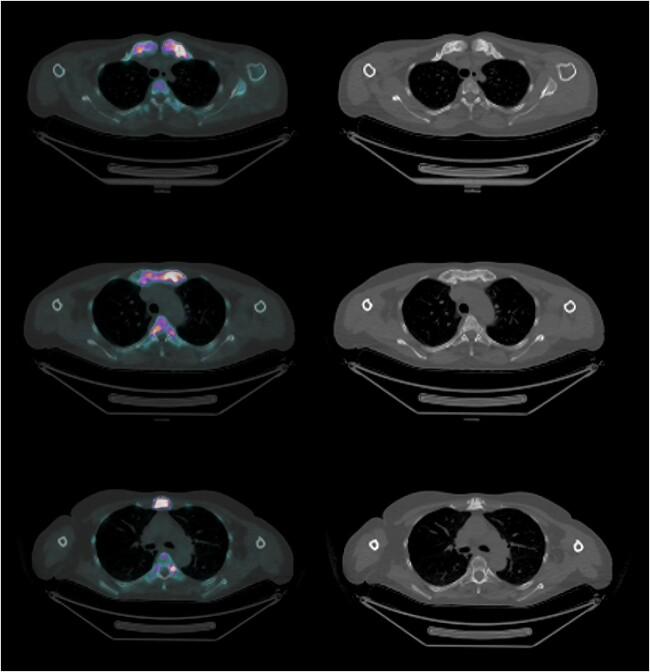

Chronic nonbacterial osteitis (CNO) is a rare disease spectrum, which lacks biomarkers for disease activity. Sodium fluoride-18 positron emission tomography/computed tomography ([F]NaF-PET/CT) is a sensitive imaging tool for bone diseases and yields quantitative data on bone turnover. We evaluated the capacities of [F]NaF-PET/CT to provide structural and functional assessment in adult CNO. A coss-sectional study was performed including 43 adult patients with CNO and 16 controls (patients referred for suspected, but not diagnosed with CNO) who underwent [F]NaF-PET/CT at our expert clinic. Structural features were compared between patients and controls, and maximal standardized uptake values (SUV [g/mL]) were calculated for bone lesions, soft tissue/joint lesions, and reference bone. SUV was correlated with clinical disease activity in patients. Structural assessment revealed manubrial and costal sclerosis/hyperostosis and calcification of the costoclavicular ligament as typical features associated with CNO. SUV of CNO lesions was higher compared with in-patient reference bone (mean paired difference: 11.4; 95% CI: 9.4-13.5; p < .001) and controls (mean difference: 12.4; 95%CI: 9.1-15.8; p < .001). The highest SUV values were found in soft tissue and joint areas such as the costoclavicular ligament and manubriosternal joint, and these correlated with erythrocyte sedimentation rate in patients (correlation coefficient: 0.546; p < .002). Our data suggest that [F]NaF-PET/CT is a promising imaging tool for adult CNO, allowing for detailed structural evaluation of its typical bone, soft-tissue, and joint features. At the same time, [F]NaF-PET/CT yields quantitative bone remodeling data that represent the pathologically increased bone turnover and the process of new bone formation. Further studies should investigate the application of quantified [18F]NaF uptake as a novel biomarker for disease activity in CNO, and its utility to steer clinical decision making.

慢性非细菌性骨炎(CNO)是一种罕见的疾病谱,缺乏疾病活动的生物标志物。18氟氟化钠正电子发射断层扫描/计算机断层扫描([F]NaF-PET/CT)是一种用于骨疾病的敏感成像工具,可提供骨转换的定量数据。我们评估了[F]NaF-PET/CT在成人CNO中进行结构和功能评估的能力。进行了一项横断面研究,纳入了43例成年CNO患者和16例对照(因疑似但未确诊CNO而转诊的患者),他们在我们的专家门诊接受了[F]NaF-PET/CT检查。比较了患者和对照之间的结构特征,并计算了骨病变、软组织/关节病变和参考骨的最大标准化摄取值(SUV[g/mL])。SUV与患者的临床疾病活动相关。结构评估显示,胸骨柄和肋骨硬化/骨质增生以及肋锁韧带钙化是与CNO相关的典型特征。与住院患者参考骨相比,CNO病变的SUV更高(平均配对差异:11.4;95%CI:9.4-13.5;p < .001),与对照相比也更高(平均差异:12.4;95%CI:9.1-15.8;p < .001)。最高的SUV值出现在软组织和关节区域,如肋锁韧带和胸骨柄关节,这些与患者的红细胞沉降率相关(相关系数:0.546;p < .002)。我们的数据表明,[F]NaF-PET/CT是一种用于成人CNO的有前景的成像工具,能够对其典型的骨、软组织和关节特征进行详细的结构评估。同时,[F]NaF-PET/CT产生的定量骨重塑数据代表了病理性增加的骨转换和新骨形成过程。进一步的研究应调查定量[18F]NaF摄取作为CNO疾病活动的新型生物标志物的应用,以及其指导临床决策的效用。